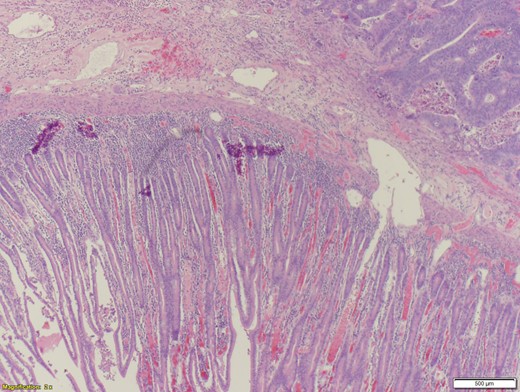

A 70-year-old female presented to the emergency department with complaints of diarrhea, vague, dull abdominal pain, unintentional weight loss and poor appetite. No hematochezia or melaena stated. Fecal occult is strongly positive in the ED. No endoscopies were found in her records. PMHx included COPD, osteoarthritis and DVT. Significant physical exam findings included mild, diffuse abdominal tenderness and RUQ palpable mass, and normal bowel sounds. Labs were significant for a hemoglobin of 5.7, hematocrit of 18.6% and CEA of 29.6. An abdominal/pelvis CT exhibited a 6 cm circumferential mass of the hepatic flexure (Figs 1–3). Two days later, a right hemicolectomy with en bloc pancreaticoduodenectomy was performed. Pathology showed adenocarcinoma stage IIIc (Figs 4–10). Post-operatively, an abdominal/pelvis CT showed bilateral pulmonary emboli and a 14 cm pelvic abscess. Bilateral lower extremity ultrasound showed low probability for DVT. Exploratory laparotomy was performed where the pelvic abscess was seen and extensive lysis of adhesions, resection of ileocolonic anastomosis for contained leak and ileostomy performed. Approximately 4 months after discharge, the patient passed away while in a long-term care facility.

When it comes to surgical intervention, there are three main methods of management of locally invasive colorectal cancers. These include hemicolectomy along with either en bloc pancreaticoduodenectomy, partial duodenectomy with either a pedicled ileal flap repair or direct suture. A 1947 study presented by Calmenson e Black, included a series of eight patients whom had locally advanced colon cancer with duodenal invasion. These patients agreed to a duodenal resection that resulted in a 0% survival rate after a year (three dying immediately in the post-operative period) [4]. The first case of right hemicolectomy with en bloc pancreaticoduodenectomy was described by Van Prohaska in 1953 [5]. Evidence shows that aggressive resection of adjacent organs along with a hemicolectomy has acceptable morbidity and mortality rates [6]. In comparison, a partial duodenal wall resection was associated with a poor outcome [7]. Even though complete resection remains controversial, microscopic examination of locally advanced colorectal cancers have shown to have a direct extension through the serosa of adjacent organs in 53.4%, whereas the remaining 46.6% showed a simple inflammatory adherence [8]. Since over 50% of locally advanced colorectal cancers resulted in a microscopic infiltration, a right hemicolectomy plus pancreaticoduodenectomy is strongly recommend for tumors that invade or are suspected to invade the duodenum and/or the pancreas [3]. However, when limited to the duodenum, a local duodenal resection is sufficient [9]. When an R0 resection was possible (achievable in 93% of all colorectal cancers), a poor outcome was avoided. However, patients with R1 or R2 resection have a 0% 5-year survival rate, compared to the 80.7% in R0 resection patients [8]. The greatest factor in the survivability of locally advanced colorectal cancer patients is when R0 resection is possible, as confirmed by Lehnert et al. [6]. Advanced age alone, apart from usually associated comorbidities, is not considered an absolute contraindication to multivisceral resection, considering the better overall results as opposed to more conservative approaches [1].